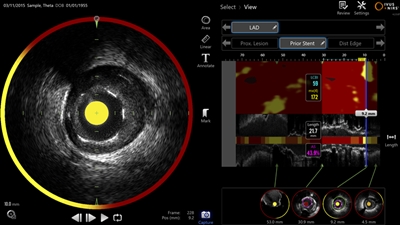

The catheter-delivered imaging tool is said to exploit the dual modality approach by both mapping the shape of blocked blood vessels and identifying the chemical composition of the plaque creating the blockage. Japan’s Pharmaceuticals and Medical Devices Agency (PMDA) approved the technology in August 2017.

The Makoto system features a “Dualpro” imaging catheter equipped with an extended ultrasound bandwidth. “By emitting and carefully processing a broad band of frequencies, the Dualpro IVUS provides best-in-class image resolution without compromising depth of field,” states Infraredx, advantages said to translate to crisper arterial imagery.

That information is combined with near-infrared spectroscopic (NIRS) data and translated into a color-coded map to identify lipid core plaque (LCP) features. That information can help cardiologists distinguish between stable and dangerous plaques inside a patient’s arteries.